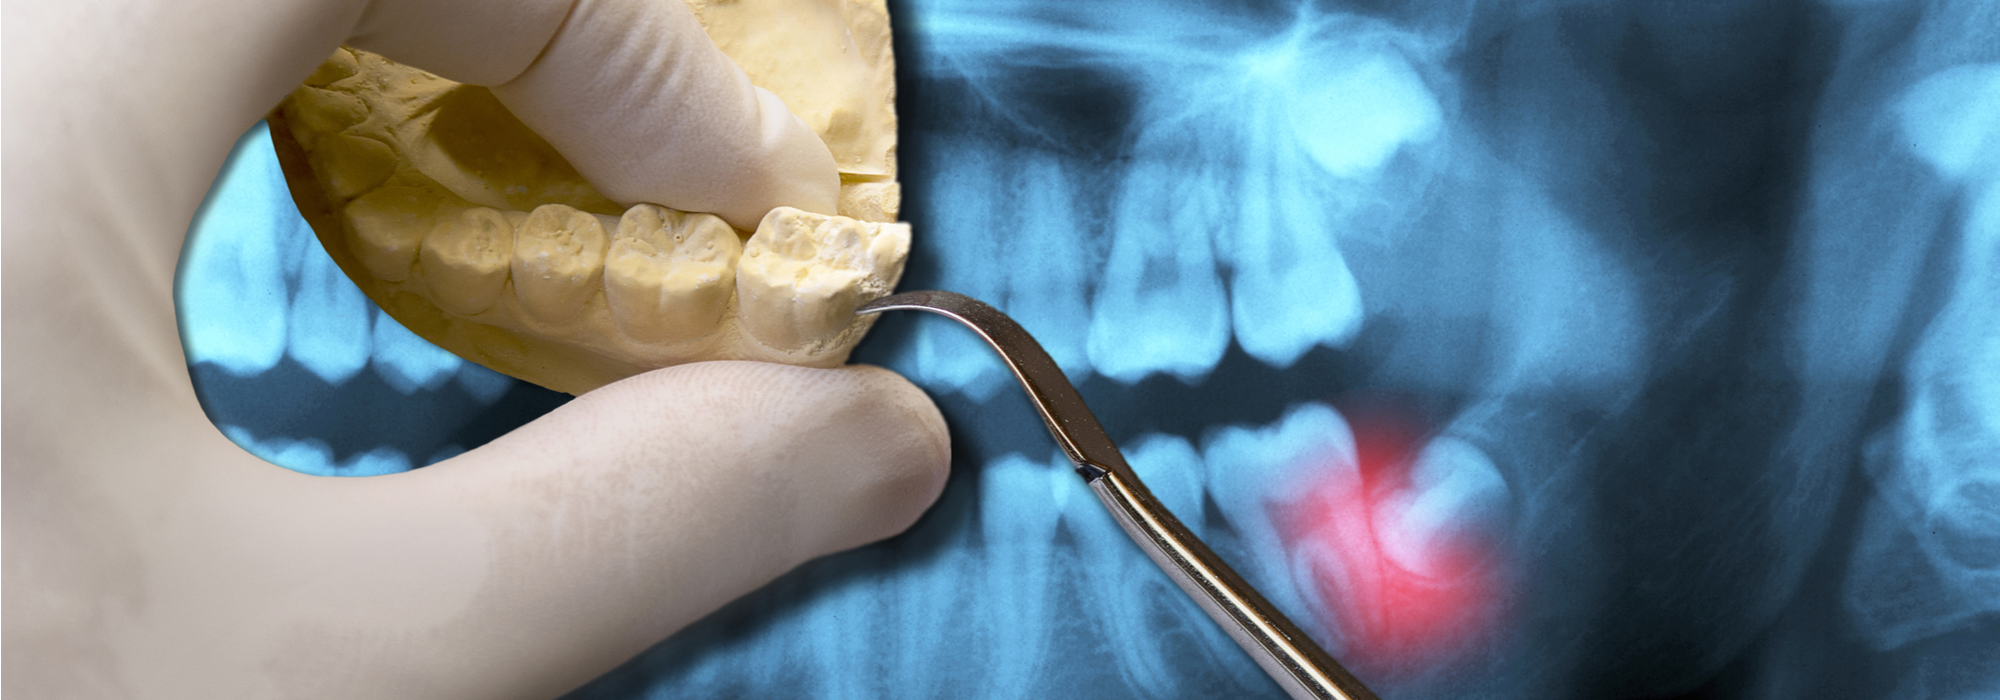

ORAL EXAMINATION FOR EXTRACTION OF WISDOM TEETHWith an oral examination and x-ra

What is an impacted Wisdom tooth?When there is not enough space for a wisdom too